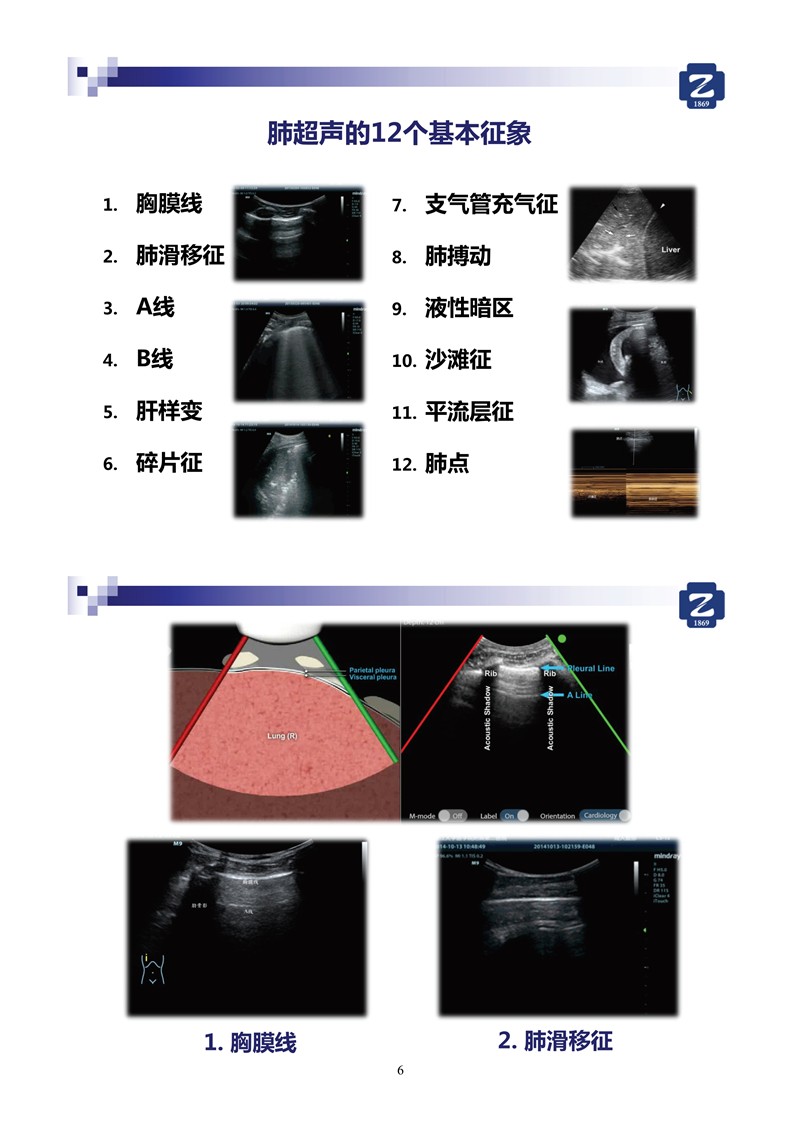

第二版新型冠状病毒肺炎超声诊断实用手册(全文)